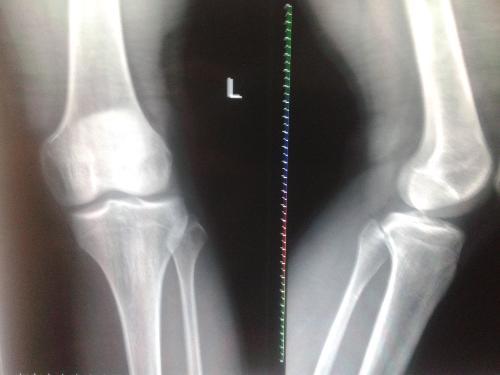

直到成年时,大多数人骨骺线开始处于休眠状态,到了20岁以后,开始逐渐趋于闭合,但是有一点需要注意的事,人体的骨骺线闭合是一个极为漫长的过程,一般18-25处于半闭合状态,25-32岁之间处于即将闭合或者闭合状态。

骨骺线是用于生长的软骨,它会随着我们的营养吸收,与内分泌激素的作用下不断的骨化。但是这一过程并非无休止的。它会随着年龄的增长而逐渐变短,当骨骺与干骺端的软骨完全骨化后,就形成一条紧密的缝,此时骨骺线完全闭合,我们就停止的人 体自然长高的过程。

到专业的生长发育医院进行全面的检查,了解自身的骨骼情况,找出导致矮小的病因 ,并且进行积极科学的治疗,这样才能真正解决矮小问题。